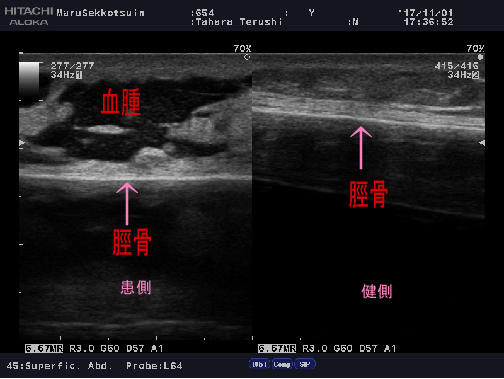

問診、触診をしっかり行いエコー検査。

受傷部位は脛骨という骨で、俗にいう「弁慶の泣き所」でございます。

ここは皮下直下に骨があり、強打すると守ってくれるクッションがないので痛い場所です、、、

検査の結果、骨には異常がなく、周囲の軟部組織の腫れ。